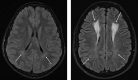

Background and purpose: Survivors of acute lymphoblastic leukemia are at risk for neurocognitive deficits and leukoencephalopathy. We performed a longitudinal assessment of leukoencephalopathy and its associations with long-term brain microstructural white matter integrity and neurocognitive outcomes in survivors of childhood acute lymphoblastic leukemia treated on a modern chemotherapy-only protocol.

Materials and methods: One hundred seventy-three survivors of acute lymphoblastic leukemia (49% female), treated on a chemotherapy-only protocol, underwent brain MR imaging during active therapy and repeat imaging and neurocognitive testing at follow-up (median, 13.5 years of age; interquartile range, 10.7-17.6 years; median time since diagnosis, 7.5 years; interquartile range, 6.3-9.1 years). Persistence of leukoencephalopathy was examined in relation to demographic and treatment data and to brain DTI in major fiber tracts and neurocognitive testing at follow-up.

Results: Leukoencephalopathy was found in 52 of 173 long-term survivors (30.0%) and persisted in 41 of 52 (78.8%) who developed it during therapy. DTI parameters were associated with leukoencephalopathy in multiple brain regions, including the corona radiata (fractional anisotropy, P = .001; mean diffusivity, P < .001), superior longitudinal fasciculi (fractional anisotropy, P = .02; mean diffusivity, P < .001), and superior fronto-occipital fasciculi (fractional anisotropy, P = .006; mean diffusivity, P < .001). Mean diffusivity was associated with neurocognitive impairment including in the genu of the corpus callosum (P = .04), corona radiata (P = .02), and superior fronto-occipital fasciculi (P = .02).

Conclusions: Leukoencephalopathy during active therapy and neurocognitive impairment at long-term follow-up are associated with microstructural white matter integrity. DTI may be more sensitive than standard MR imaging for detection of clinically consequential white matter abnormalities in childhood acute lymphoblastic leukemia survivors treated with chemotherapy and in children undergoing treatment.